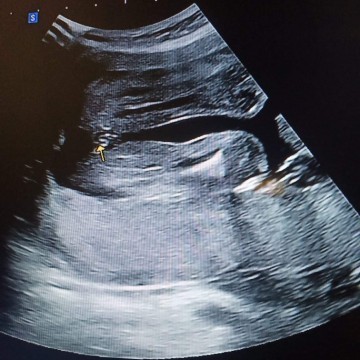

ท้อง6เดือนแล้ว แต่ไม่รู้เพศเลย

6เดือนแล้วยังไม่รู้เพศเลยค้าาา ใครท้องกัเดือนแล้วบ้างคะ🙏😍❤️#ใครมีประสบการณ์